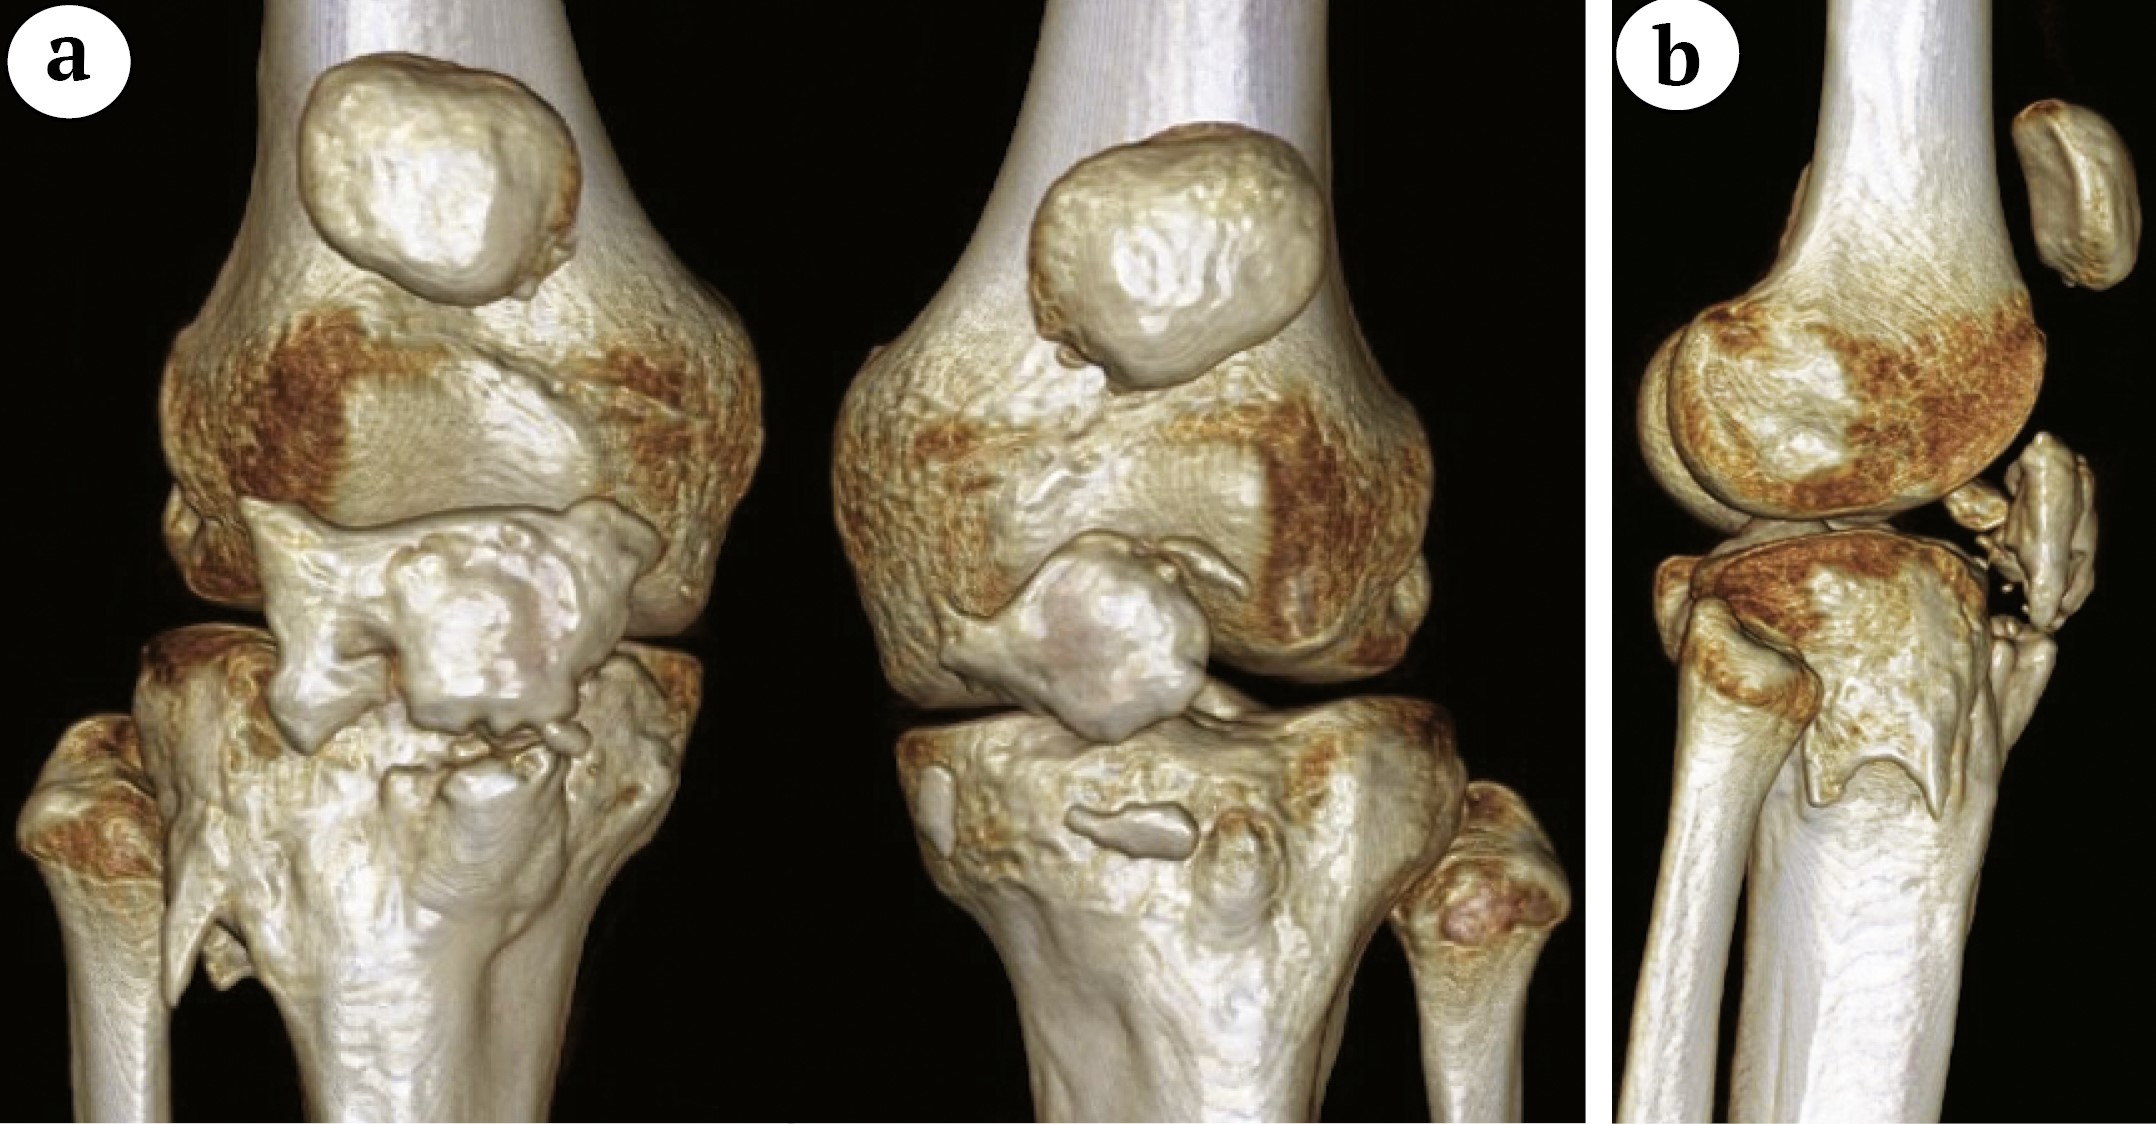

Компьютерная томография отражает детально топографию, количество и геометрические характеристики оссификатов, позволяет спланировать последующее хирургическое лечение (рис. 3, 4).

Рис. 3. Компьютерные томограммы коленных суставов с 3D-реконструкцией пациента 3: а — двусторонняя патология; b — в правом суставе визуализируется фрагмент оссификата с внутрисуставным расположением

Figure 3. CT of the knee joints of patient 3 with 3D reconstruction: a — bilateral pathology; b — an ossification fragment with an intraarticular location is visualized in the right joint

Рис. 4. Компьютерная томограмма коленных суставов с 3D-реконструкцией пациента 4: правосторонняя фрагментарная оссификация связки надколенника

Figure 4. CT of the knee joints of patient 4 with 3D reconstruction: right-sided fragmentary patellar tendon ossification